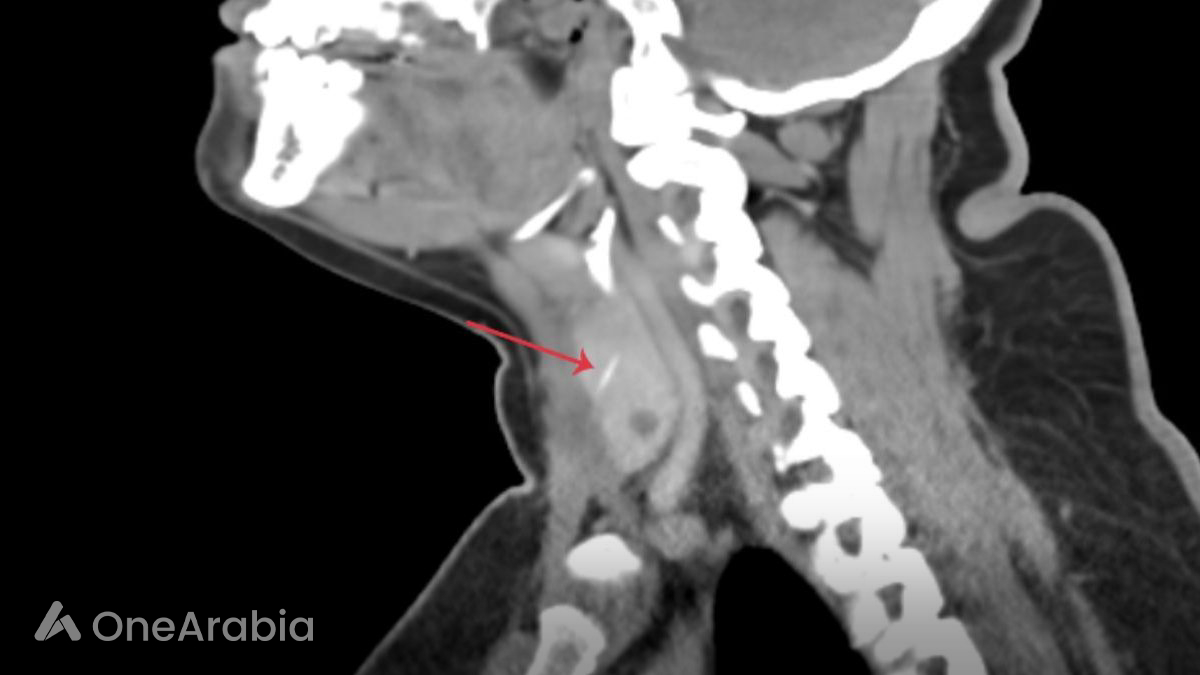

Initial examinations using a laryngopharyngoscope revealed no visible foreign body. However, a subsequent sonogram identified a suspicious linear object, leading to her referral to Aster Hospital Mankhool. A CT scan with contrast confirmed the presence of a 3cm fish bone embedded in the right thyroid lobe, penetrating the strap muscle.